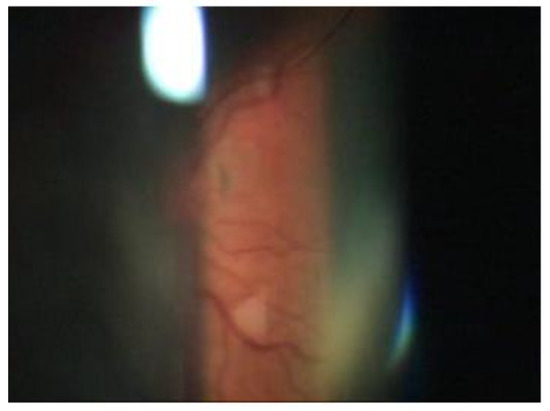

A 65-year-old woman presented to our attention complaining of two days of swelling in the right eye, reduced visual acuity, diplopia, and mild pain. The history was negative for recent trauma and confirmed good general health conditions. The physical examination revealed complete ophthalmoplegia (Figure 1), non-pulsatile reducible axile exophthalmos, eyelid edema, significant chemosis, and conjunctival ectropion (Figure 2). Visual acuity at the time of admission was 5/10 in the right eye and 10/10 in the left eye. The biomicroscopic examination of the anterior segment showed an important stasis of the episcleral vessels (Figure 3) and a shallow anterior chamber, whereas the fellow eye was unremarkable.

Figure 3. Dilatation of the episcleral vessels.